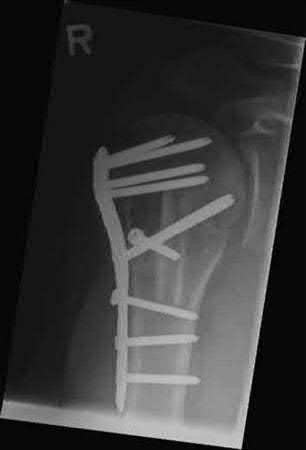

A 64-year-old woman is thrown off a horse, sustaining the injury shown in Figures A and B. She undergoes surgical fixation as seen in Figures C through E. What is the most commonly reported complication of this procedure?

1) Axillary nerve injury

The patient in the scenario has a 2-part proximal humerus fracture treated with a locking plate as seen in Figures A-E. The most common complication with the use of this implant is screw penetration. The terms screw cut out and penetration are often used interchangeably in the literature with cut out appearing more frequently in reports regarding intertrochanteric fractures.

Owsley et al retrospectively reviewed 53 proximal humerus fractures treated with locking plates and the same post-operative protocol. The most common complication was screw cut out or penetration, followed by varus displacement. They concluded that 3 and 4-part fractures in patients over 60 years have a higher incidence of failure.

Agudelo et al retrospectively reviewed 153 patients at a level-one trauma center treated with proximal humerus locking plates, investigating modes of failure for the implant. They determined that varus malreduction (head-shaft angle